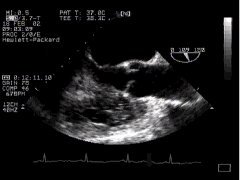

1. Two chamber view (LA, LV, MV) - 'TG 2 Chamber'

2. The anterior mitral leaflet (aml) is well seen, as well as the left ventricular and atrial chambers. The inferobasal portion of the left ventricle is particularly well seen in this view - perhaps the major justification for this particular part of the TOE examination! (The inferobasal part is that part of the LV in the upper portion of the image, close to the probe). Remember that in the visible human from which these anatomical sections were taken, the left side is particularly poorly filled, and thus the LV cavity appears much plumper in the echo image. Compare the above with the two-chamber mid-oesophageal view.